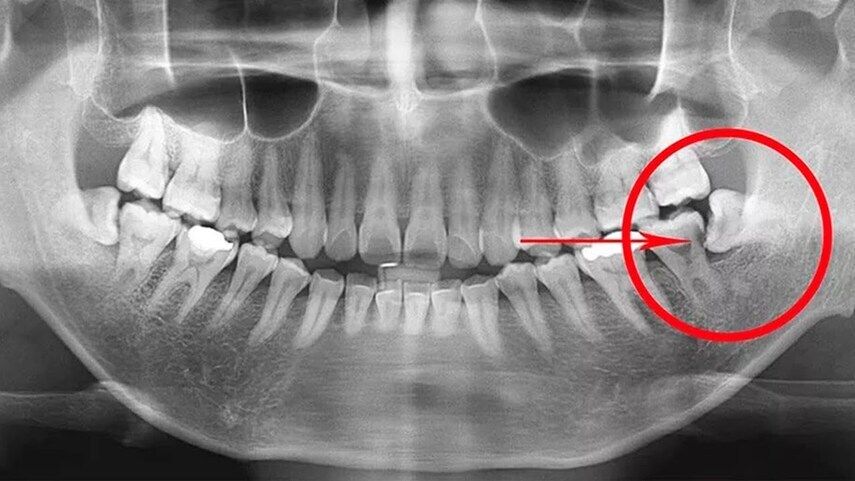

Первым делом я отправлю вас на снимок. Это может быть прицельный рентген или, в более сложных случаях, компьютерная томография (КТ). Зачем? Мне нужно видеть, что скрыто в десне. Снимок — это моя карта. Я вижу количество корней, их форму, изгибы, положение относительно нервов и соседних зубов. Без этого «навигатора» начинать работу нельзя. Иногда, чтобы увидеть все трещинки и каналы, мы используем специальное оборудование, например, проводим лечение зубов под микроскопом, что гарантирует максимальную точность.

Ах, эти «восьмерки»! Удаление их корней часто бывает сложнее. Почему? Они расположены далеко, доступ к ним затруднен. Часто их корни бывают изогнутыми, переплетенными между собой или сросшимися с костью. Поэтому удаление корня зуба мудрости требует от хирурга особого мастерства и часто — использования КТ для точного планирования.